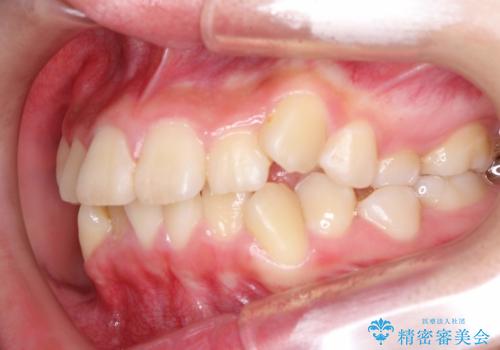

- 上下左右4本の小臼歯を抜歯、ラビアル・ワイヤー矯正を計画した。

抜歯をして第1小臼歯分のスペースを獲得することにより、ガタつきの改善と前歯のリトラクトをおこない、横顔の印象もすっきりとし、整ったEラインを作ることができました。